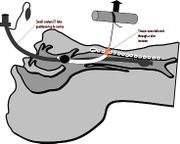

| 04:57, 23 October 2018 | Trans cerv.jpg (file) |  |

30 KB | Drtbalu | |